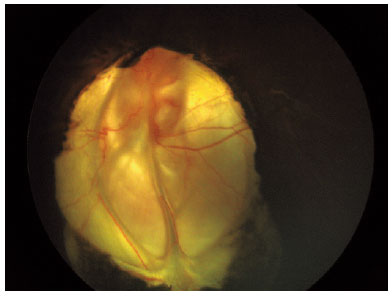

The anterior segment examinations revealed colobomas of the iris, optic nerve, and retina in the inferior quadrant of the oculus uterque (Figure 3). Ocular ultrasonography revealed no retrobulbar cyst, and the axial length was 20 mm in the OD and 22 mm in the OS.

14-fig03.jpg)